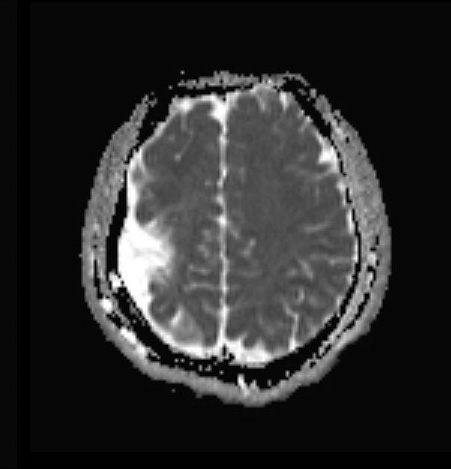

Common Neurological Conditions Impacted by Disparities

While all brain conditions are challenging, disparities can make them even harder to manage. Lack of access to proper nutrition, specialized care, and resources can worsen symptoms and slow recovery for many common neurological issues.